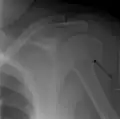

A fracture of the greater tuberosity as seen on AP X ray -

A fracture of the greater tuberosity of the humerus -

Fracture of the greater tuberosity of the humerus -